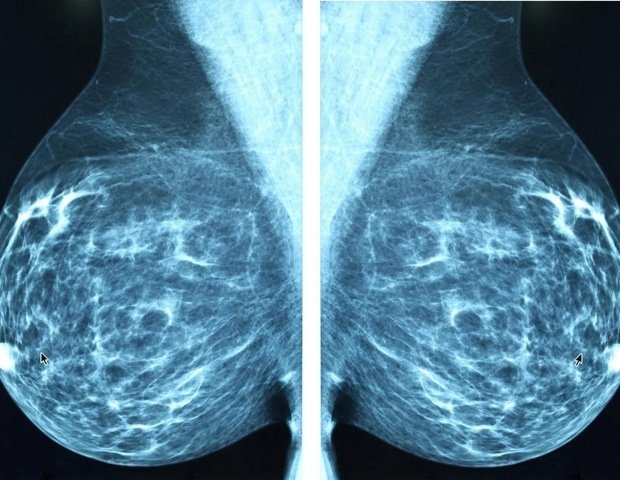

Although a common procedure, mastectomy, which involves removing one or both breasts, is an important surgery that requires long -term monitoring. More than a quarter of patients with breast cancer usually undergo mastectomy, and many patients remain in the hospital for shorter periods after surgery*- a tendency that has prompted researchers to analyze the results of patients after systematically.

From nearly 3,000 studies they identified, the researchers analyzed 20 studies that met their integration criteria, examining the effects of mastectomy on quality of life, sexual health and psychosocial well -being. All articles focused on the experience of women with breast cancer 1-3 stages. Studies involving women with stage 4 breast cancer, as well as women elected for prophylactic mastectomy to reduce the risk of cancer, were excluded from study due to separate needs and different overall medical decisions for these patients.